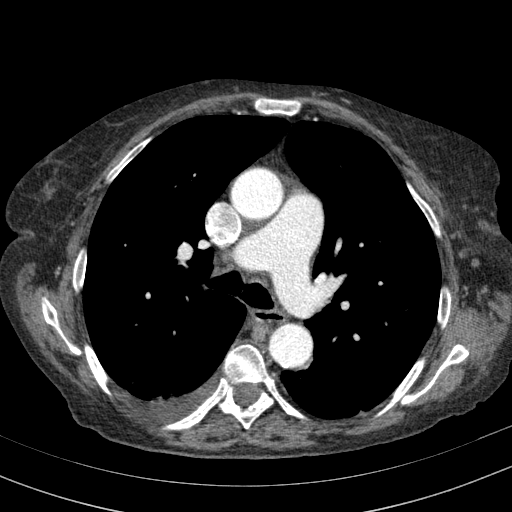

Original VENOUS CT scan

Full window (WL 1023.5, WW 4095 β†’ Low βˆ’1024, High +3071)

Lung window (WL -600, WW 1500 β†’ Low βˆ’1350, High +150)

Mediastinum window (WL 40, WW 400 β†’ Low βˆ’160, High +240)